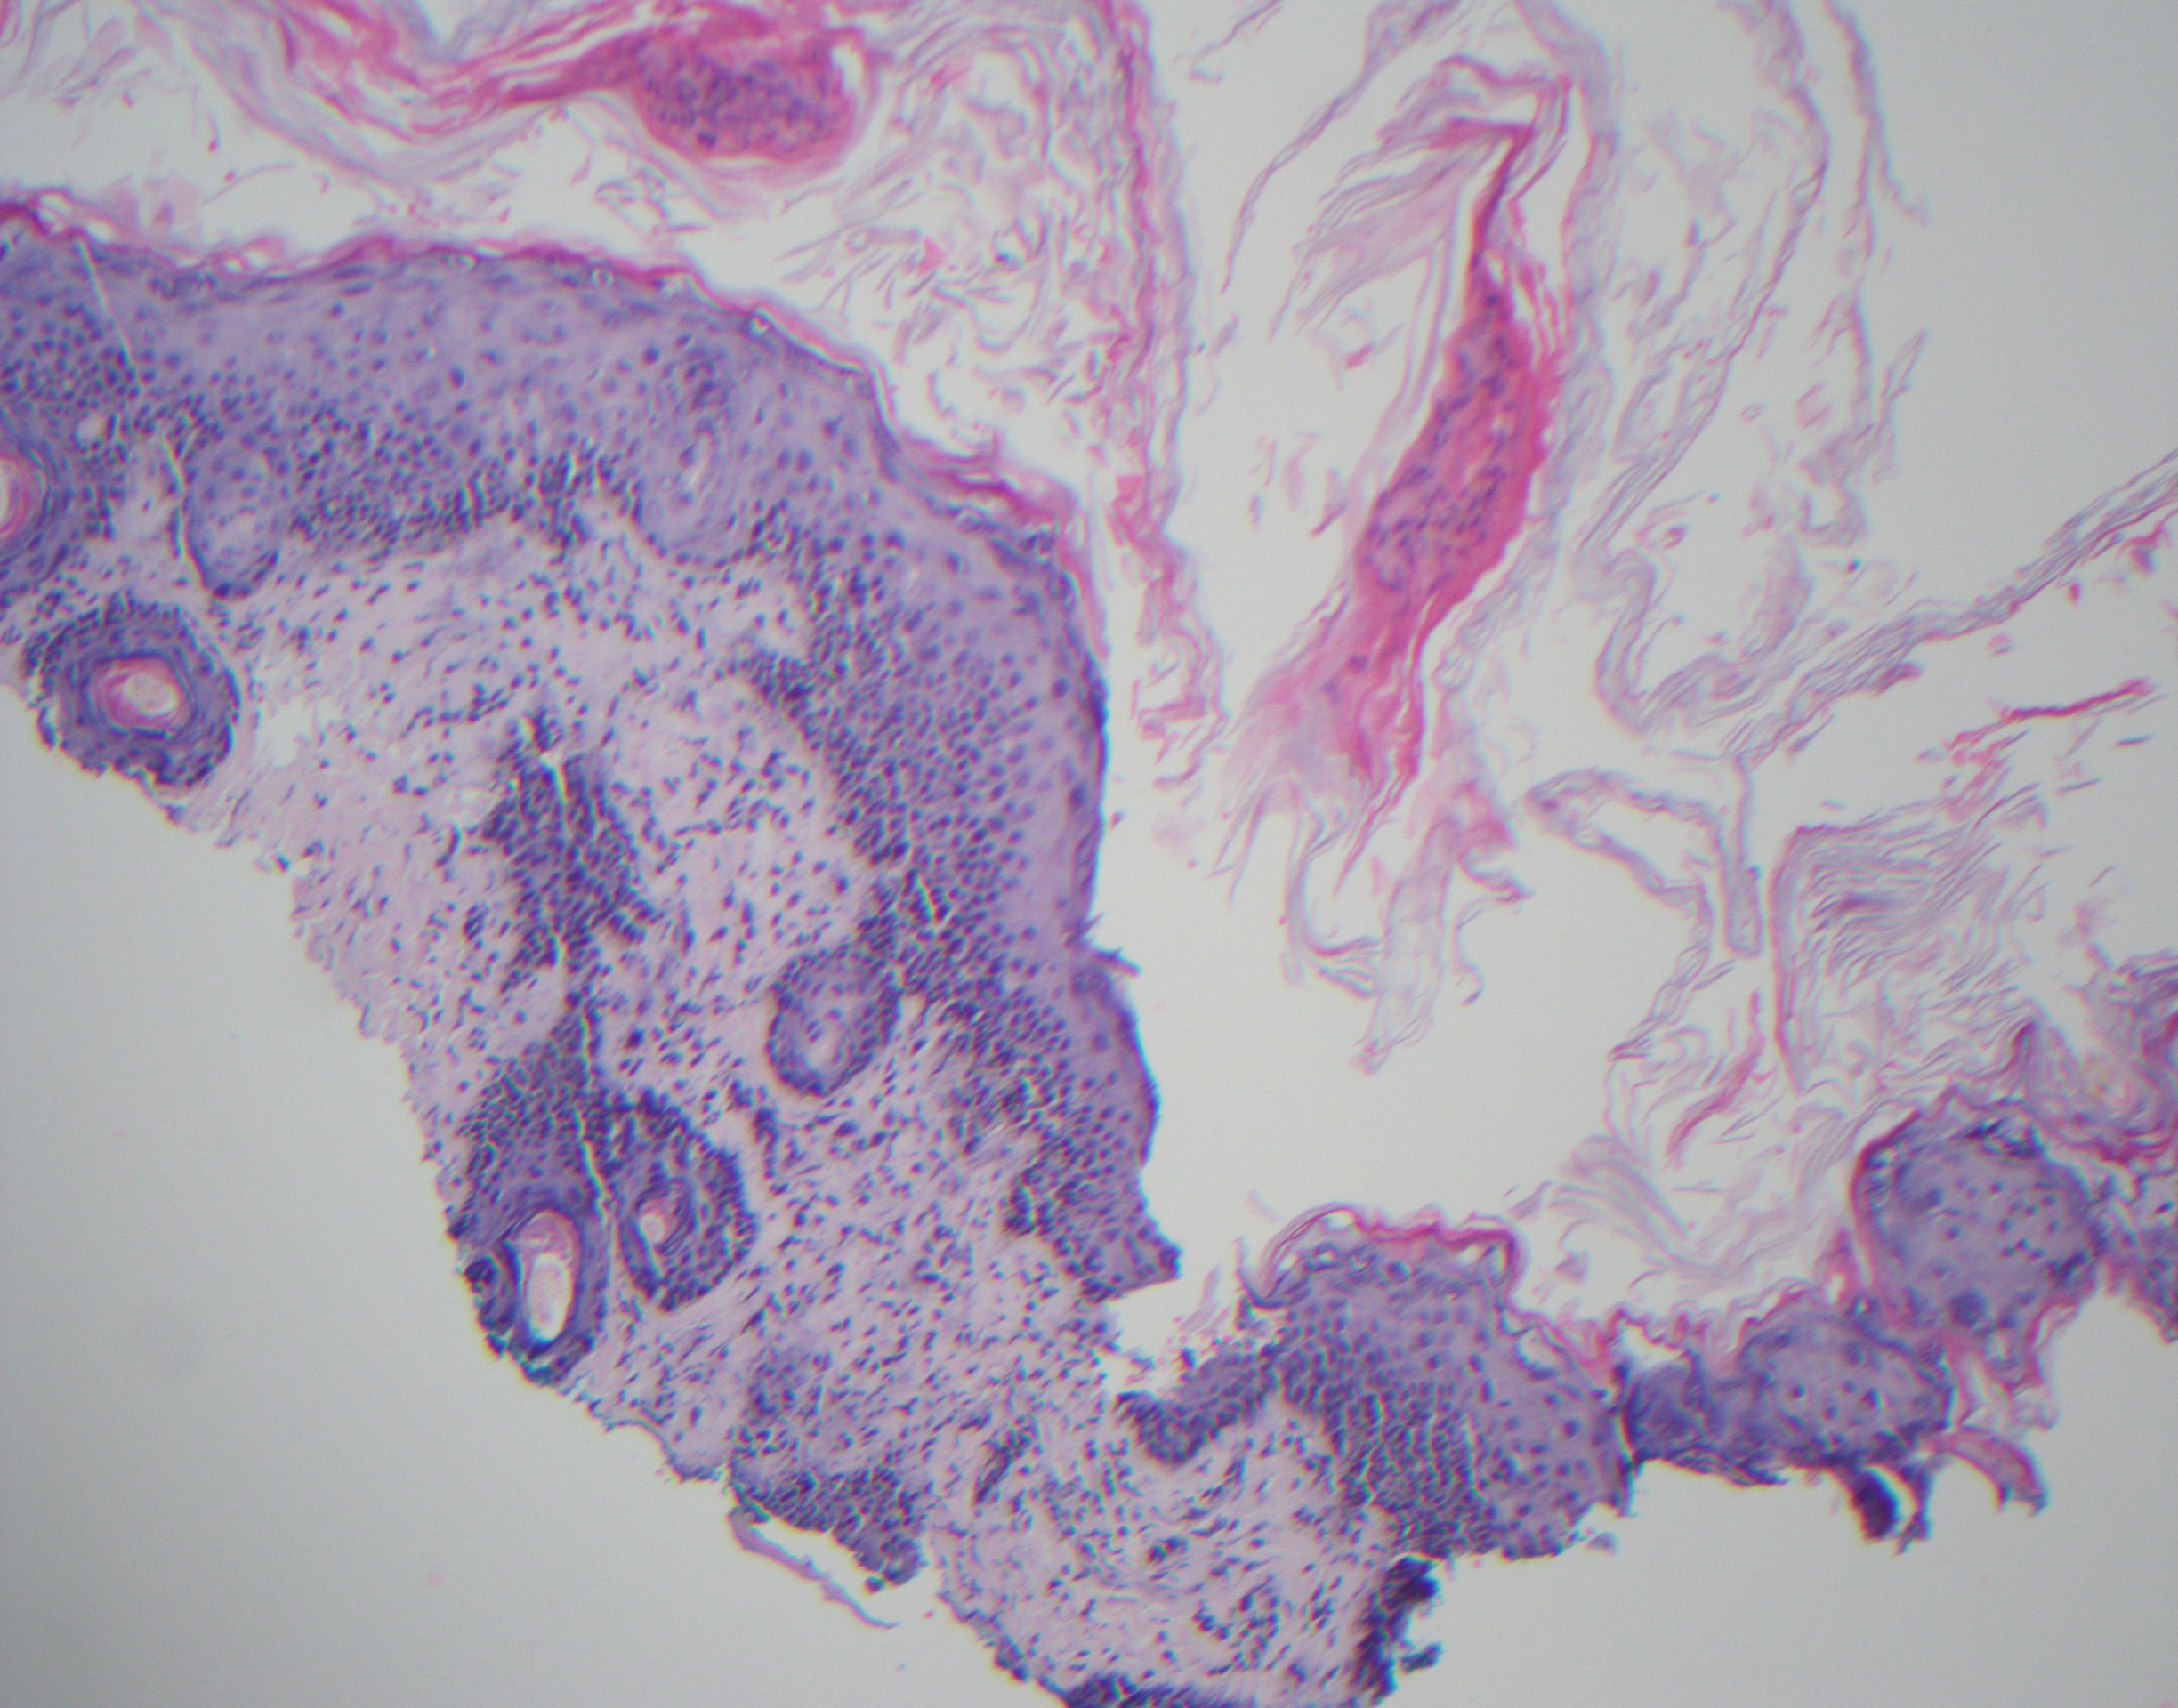

Diagnostic tests. A punch biopsy was done of one of the scalp lesions and was stained with hematoxylin and eosin (Figure 3) as well as with colloidal iron (Figure 4). The biopsy revealed atrophic epidermis and interface dermatitis with positive staining for mucin, findings suggesting a diagnosis of neonatal lupus erythematosus (NLE). Results of a complete blood cell count and electrocardiography were normal.

Figure 3. Hematoxylin and eosin stain results of a biopsy specimen.